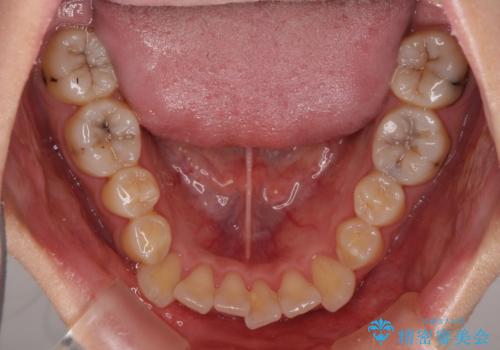

元々奥歯に負担のかかる咬み合わせですり減っていたため、仕上がった歯並びでも奥歯が咬んでいないように見えましたが、実際にはしっかりと咬合しており、患者様本人も咬んだ感触に違和感はないとのことでした。